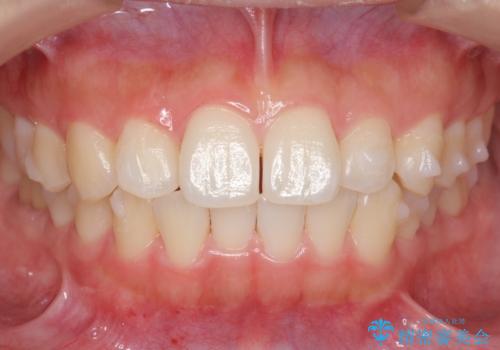

インビザライン モニターで前歯をきれいに

- 前歯のがたつきをきにされていました。

上下の前歯をやすりがけする処置(IPR)を行い、前歯の並びを出っ歯にしないようにしながら整えました。

症状が軽度であるためモニター採用になりました。